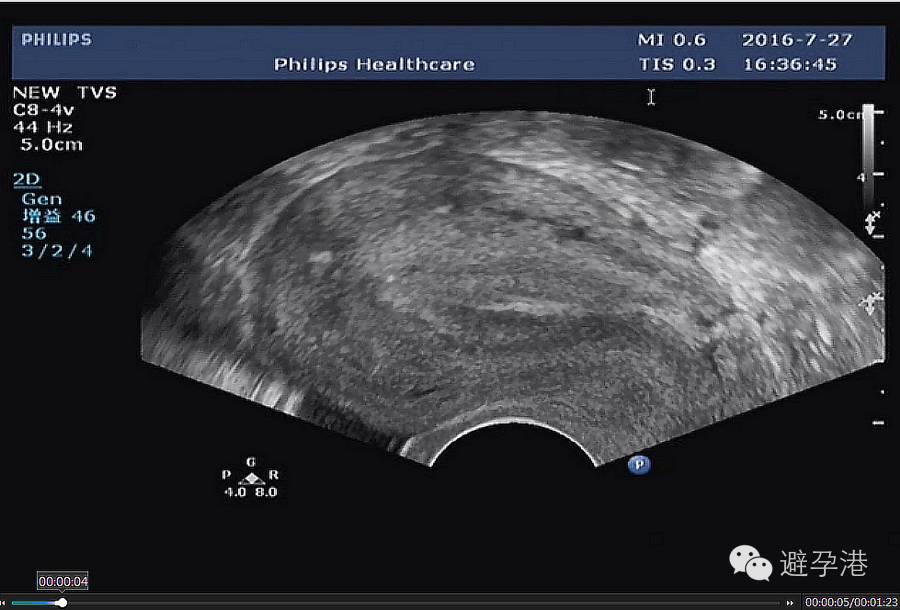

1.纵切面:在宫内可显示出串珠状六个亮点的强回声带。

吉妮致美环怎么样吉妮致美节育器超声图像解读_https://www.jmylbn.com_新闻资讯_第2张

吉妮致美环怎么样吉妮致美节育器超声图像解读_https://www.jmylbn.com_新闻资讯_第3张